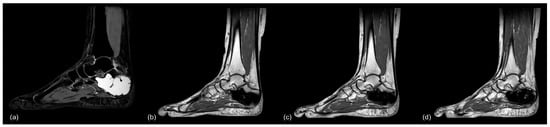

Complications were predominantly related to the use of Cerament©, leading to a 90% complication rate (9/10) in patients treated with this particular injectable bone substitute. These complications included DWH with “white-out” in 7/10 cases, one case of DWH without “white-out”, one revision surgery, and one suralis neuropraxia. As the “white-out” phenomenon has been repeatedly observed in various non-tumorous indications in our clinical practice, and excessive white drainage after the use of Cerament© does not seem to be limited to its use in aneurysmal bone cysts, we have stopped using this product entirely. Figure 9 and Figure 10 show examples of the gradual loss of Cerament© over time, leading to “white-out”, insufficient stabilization of the bone cavity, and cyst recurrence. These specific complications did not occur with other injectable bone substitutes. However, repeated MRI performed after treatment with two different types of calcium phosphate bone cement (case 6 and 25, Quickset© and Innotere©) did not demonstrate any postoperative signs of osseous ingrowth or bony transformation at 36 and 91 months (Figure 6b and Figure 11), respectively.

Figure 11.

MR-imaging of case 26: (a) preop (PD TSE sag), (b) 6.5 months postop (T1 TSE sag), (c) 13 months postop (T1 TSE sag), and (d) 40 months postop (T1 TSE sag), showing no signs of osseous remodeling after more than 3 years postoperatively.